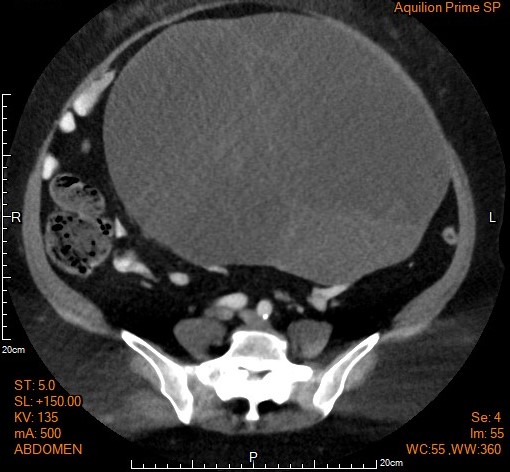

▎案例分享

58歲女性近三個月出現腹脹和體重增加,一開始患者症狀並未引起當時的高度警覺,經婦產科醫師檢查懷疑卵巢腫瘤,並進行腹部電腦斷層(CT)檢查(如圖片),結果發現約30公分的卵巢腫瘤。隨後,醫生決定安排手術治療。